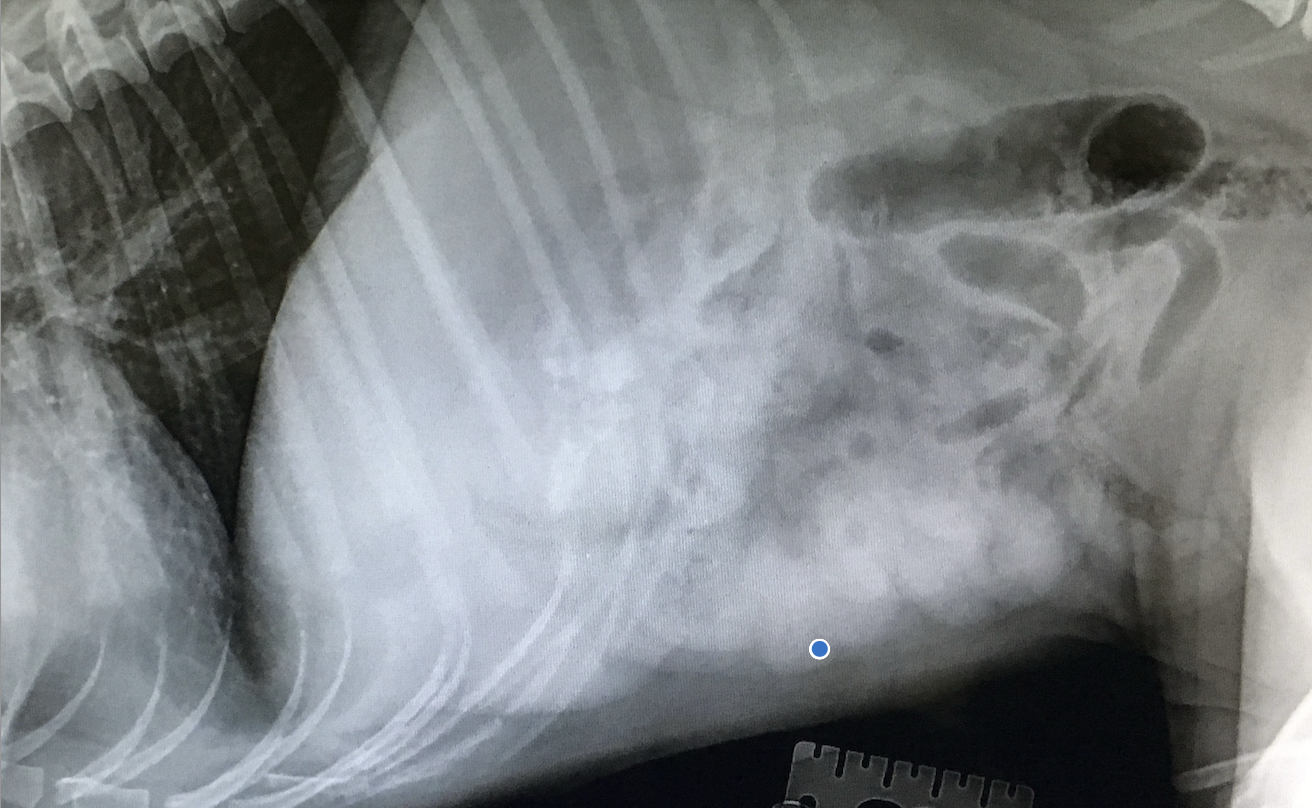

Abgesehen von der klinischen Evaluierung ist die bildgebende Diagnostik ausschlaggebend. Sowohl röntgenologisch als auch sonographisch können LFB dargestellt werden, wobei die Interpretation beim Ultraschall eine sehr hohe Sensitivität aufweist. Beim Röntgen machen sich luftgefüllte Kommas bemerkbar oder sogar die Plikation des Darmes (“string of pearls”). Sollte man freie Luft im Abdomen finden, so ist dies ein Indiz für eine Perforation.